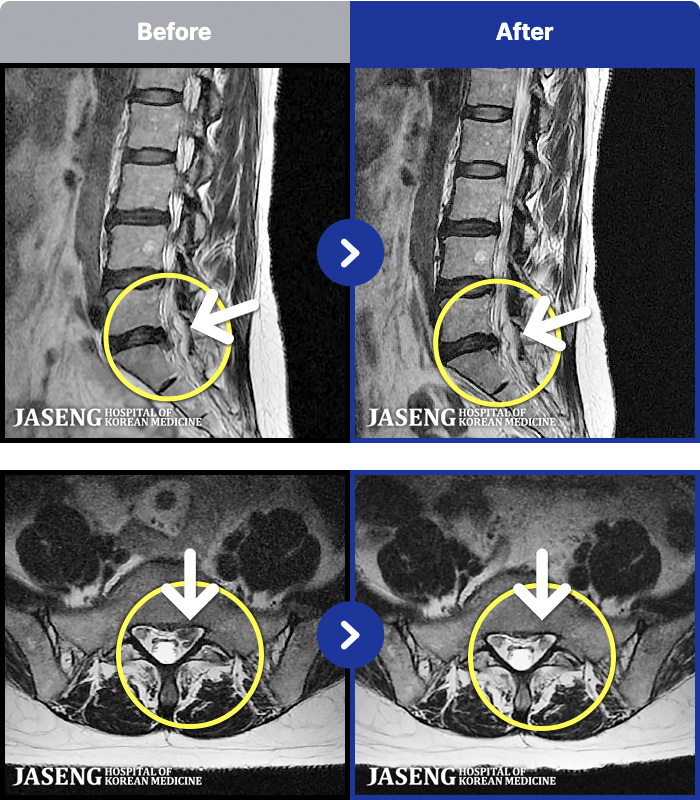

MRI ġ

54 MRI ũ ʸ Ȯϼ.

[Կñ:25.03.29~25.07.17]

[_㸮ũ] 㸮

No.52

ȸ 62

2026.01.06